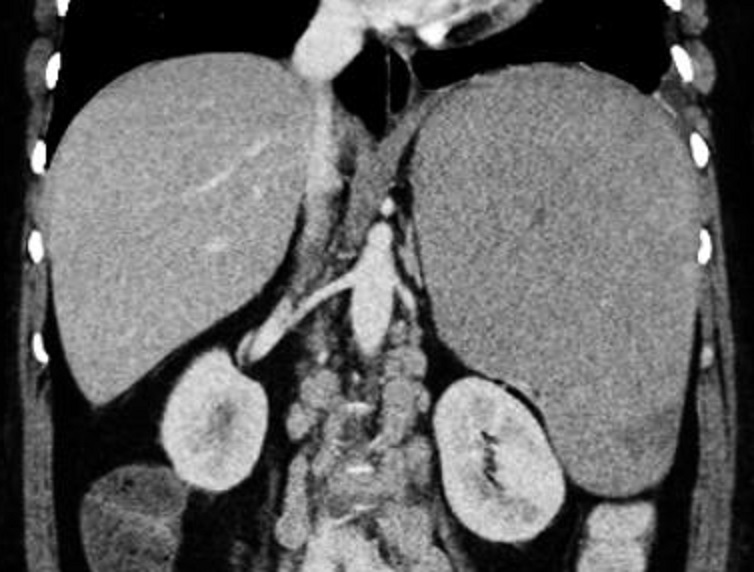

Image radiologique de laceration de la rate, le rein et du

foie . Aspect radiologique de laceration est ligne hypodense

peut en s'observe sur la rate , le rein et fu foie ..

Rein gauche est tres voluneuse Coupe TDM

coronal de l'abdomen au temps veineuse |